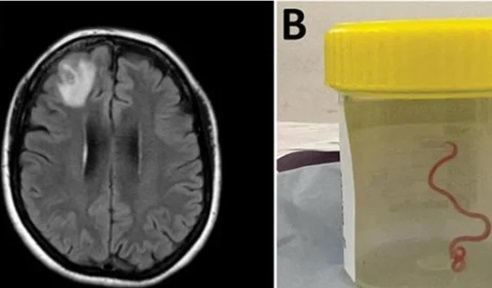

وبعد عدة أشهر، تطورت أعراضها إلى نسيان واكتئاب دخلت على إثرهما إلى مستشفى في العاصمة الأسترالية، حيث كشف فحص التصوير بالرنين المغناطيسي عن شيء غير عادي في الفص الأمامي الأيمن من دماغها.

بعد إجراء جراحة طبيبة للسيدة الأسترالية، لم تتوقع الطبيبة إخراج دودة طفيلية حية طولها 8 سنتيمترات (3 بوصات) كانت تتلوى بين ملقطها، فكيف اكتشفتها الطبيبة؟.

ووفقا لبيان صحفي صادر عن الجامعة الوطنية الأسترالية ومستشفى كانبيرا، أكدت الاختبارات الجزيئية أنها أوفيداسكاريس روبرتسي، وهي دودة مستديرة توجد عادة في الثعابين.